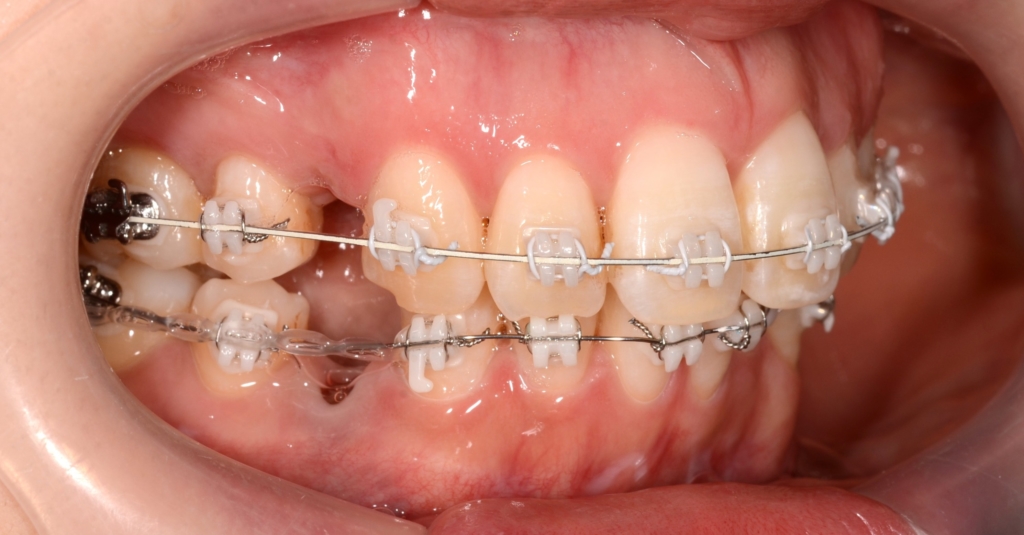

マルチブラケットシステム(ハーフホワイトtype)で矯正を開始。

【治療開始】

【経過】